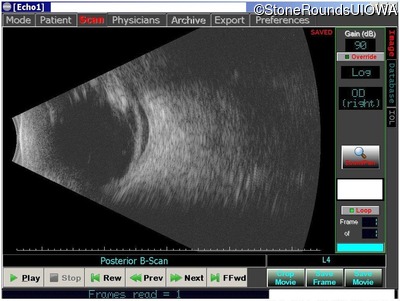

B-Scan Ultrasonography - Left - unknown

Exemplar